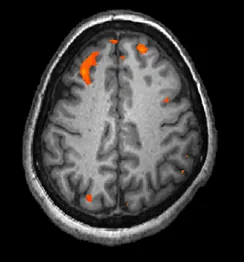

In magnetic resonance imaging (MRI), a person is placed inside a machine that generates a strong magnetic field. The magnetic field causes the hydrogen atoms in the body’s cells to move. When the magnetic field is turned off, the hydrogen atoms emit electromagnetic signals as they return to their original positions. Tissues of different densities give off different signals, which a computer interprets and displays on a monitor. Functional magnetic resonance imaging (fMRI) operates on the same principles, but it shows changes in brain activity over time by tracking blood flow and oxygen levels. The fMRI provides more detailed images of the brain’s structure, as well as better accuracy in time, than is possible in PET scans (Figure 3.28). With their high level of detail, MRI and fMRI are often used to compare the brains of healthy individuals to the brains of individuals diagnosed with psychological disorders. This comparison helps determine what structural and functional differences exist between these populations.

A brain scan shows brain tissue in gray with some small areas highlighted red.

Figure 3.28 An fMRI shows activity in the brain over time. This image represents a single frame from an fMRI. (credit: modification of work by Kim J, Matthews NL, Park S.)